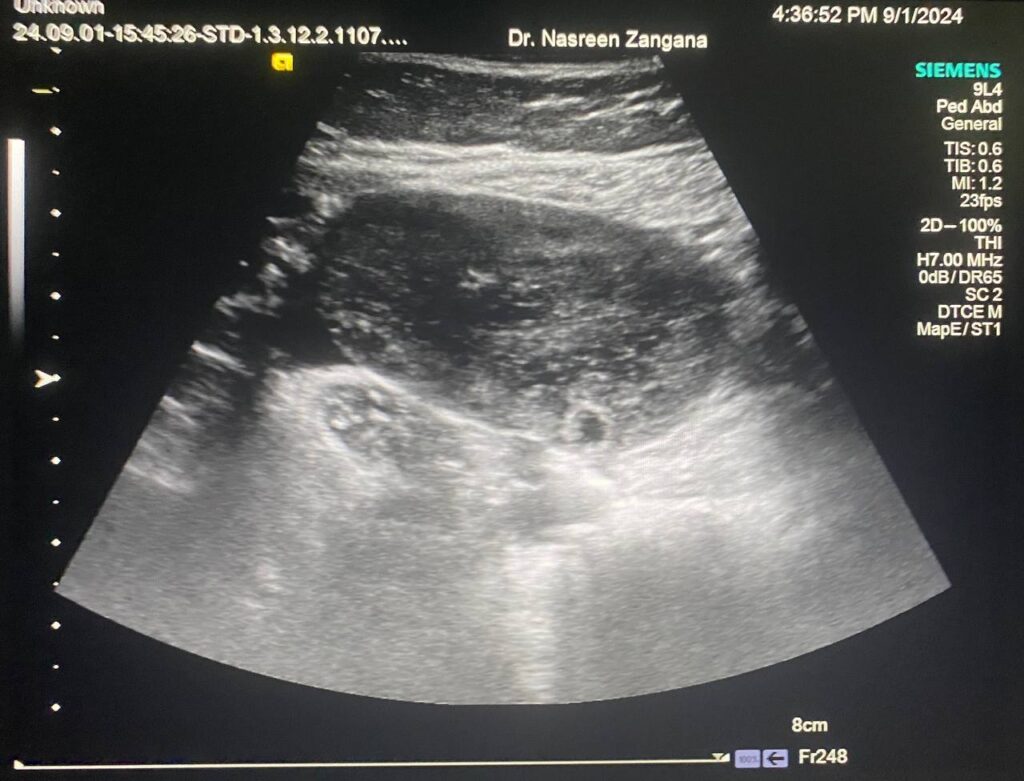

10 years old girl, right ovary enlarge in size with peripheral follicles & little vascularity within, mostly Ovarian Tosrion ?